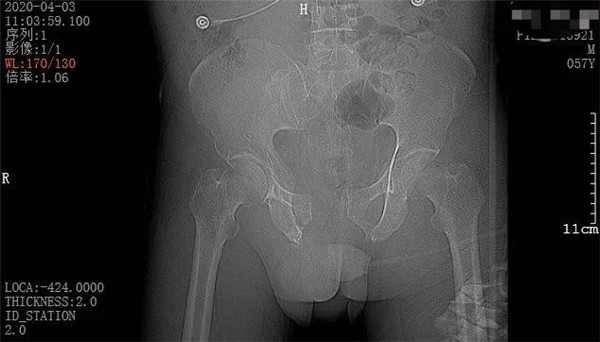

4月3日一早,和往常一樣,家住六橫的趙大叔騎著三輪車去買菜,誰知經(jīng)過下坡路時(shí)剎車失靈,趙大叔重重地撞上了一根柱子后,三輪車壓倒了他身上。趙大叔頓時(shí)感覺身體疼痛不已,無法轉(zhuǎn)身、站立。在路過市民的幫助下,他迅速被送至當(dāng)?shù)蒯t(yī)院。經(jīng)CT拍攝顯示,趙大叔骨盆骨折、腹腔積血。此時(shí),大叔突然出現(xiàn)了呼吸急促、血壓不穩(wěn)定等情況,聞?dòng)嵍鴣淼募覍佼?dāng)即表示要到廣安醫(yī)院治療,并火速聯(lián)系車子送往我院。

內(nèi)科繼續(xù)加強(qiáng)補(bǔ)液、輸血及升壓藥物應(yīng)用,穩(wěn)定患者生命體征。超聲科在經(jīng)過床邊檢查后,發(fā)現(xiàn)患者膀胱內(nèi)積血、肝脾未破裂,腹腔積血為血腫形成,暫不考慮開腹探查。普外科周正主任分析病情后考慮病人存在膀胱損傷,立即對(duì)其進(jìn)行導(dǎo)尿,保證尿液引流通暢,促進(jìn)膀胱功能恢復(fù)。骨科醫(yī)生立即對(duì)患者進(jìn)行骨盆外固定帶固定骨折部位,牽引復(fù)位,以避免骨折端進(jìn)一步錯(cuò)位導(dǎo)致二次損傷。